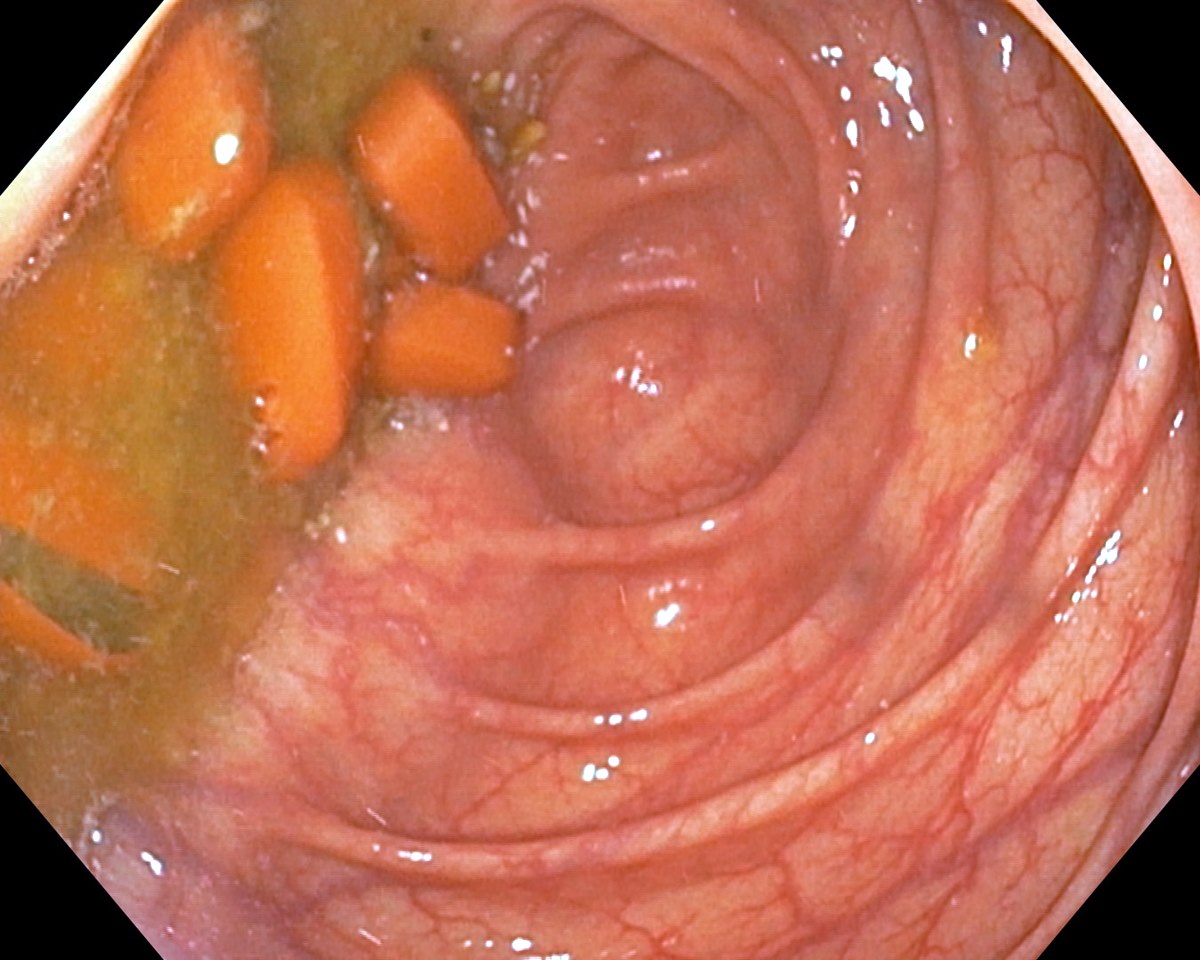

Asacol Tablets in the Caecum, Inactive Ulcerative Colitis

Asacol Tablets in the Caecum, Inactive Ulcerative Colitis. Just click on a picture!